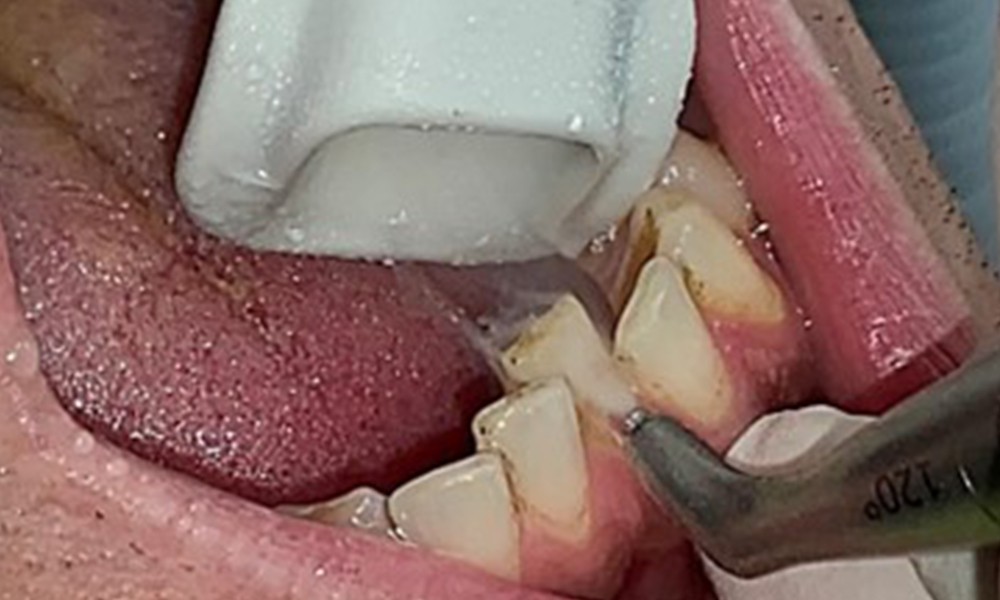

Instruction and motivation are important components of these appointments. Good home-based intraoral hygiene behaviour and understanding are important for patients. Plaque accumulation is particularly evident in the cervical regions (Fig. 8).

These must be discussed with the patient, and improvements to the teeth-brushing technique must be practised. A soft toothbrush attachment is recommended for home-based intraoral hygiene due to the presence of erosions and attritions.

The objective would be to control disease risk by removing supragingival and subgingival biofilm. The instruments can be selected based on patient needs. First, calculus and any concretions must be removed using ultrasonic and/or manual instruments (Fig. 10).